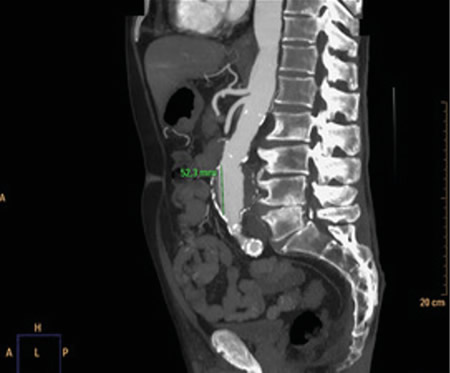

No es solo dolor lumbar: manifestación atípica del aneurisma de aorta

Not just low back pain: atypical manifestation of aortic aneurysm

La rotura de aneurisma de aorta supone el síntoma principal en hasta un 25 % de los casos de la patología de aneurisma de aorta, que constituye una entidad potencialmente mortal. También puede aparecer con menor prevalencia como lumbalgia, coxalgia e, incluso, gonalgia, no comentándolo como dolor vertebral o neuropático, sino como irritación a nivel de psoas ilíaco como primera sintomatología.

Se estima que solo en un 50 % de los casos aparece la triada clásica del aneurisma, por lo que es necesario tener un alto nivel de alerta para sospecharlo, ya que la hipovolemia puede estar contenida por un hematoma peritoneal.

Figura 1